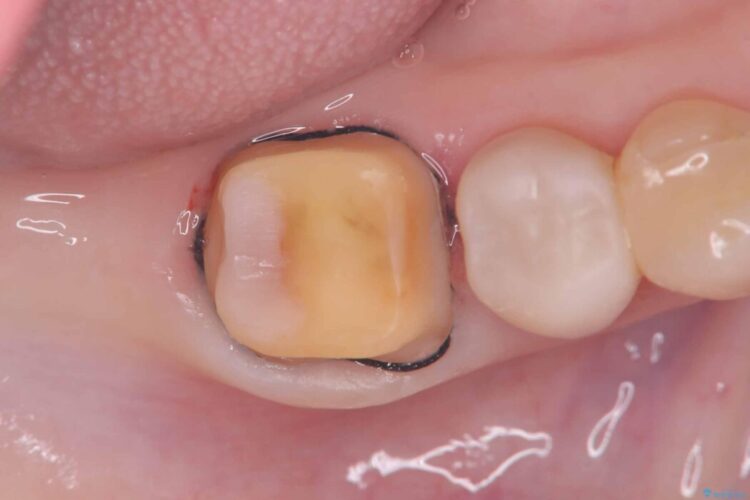

再治療にあたり、再度インレーで修復する方法と、歯全体を覆うクラウンによる修復の選択肢をご説明しました。

破折の再発防止および歯質保護を最優先に考え、オールセラミッククラウンによる治療を計画しました。

そのため今回は、歯をしっかり保護し、長期的な安定を図るために、オールセラミッククラウンによる修復を行いました。

クラウンにすることで、噛む力を分散しながら歯を保護できるため、再び割れてしまうリスクを大きく下げることが可能です。